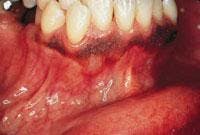

CASE 7

Peripheral ossifying fibroma (POF)

1. Where is the POF likely to occur?

a. hard palate

b. gingiva

c. floor of mouth

d. any of the above

2. What is the appearance of the POF?

a. pale pink or reddish color

b. sessile or pedunculated

c. smooth surface

3. What lesion may be confused with the POF?

a. pyogenic granuloma

b. peripheral giant cell granuloma

c. irritation fibroma